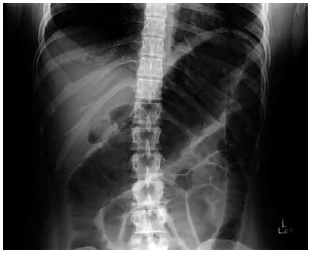

Homem de 24 anos apresenta quadro de diarreia sanguinolenta há 2 semanas, com até 10 evacuações por dia, associado a dor e distensão abdominal inferior. Ele tem colite ulcerativa extensa de 5 anos de duração e os medicamentos em uso são infliximabe, azatioprina e prednisona. Ao exame físico: o paciente parece doente; temperatura: 38,3 ºC; pressão arterial: 90 x 60 mmHg; frequência cardíaca: 110 bpm; o abdome está distendido com defesa à descompressão; os sons intestinais são hipoativos. Exames séricos: hemoglobina: 10 g/dL; leucócitos: 16 000/mm3; ureia: 26 mg/dL. A radiografia abdominal realizada é mostrada a seguir.